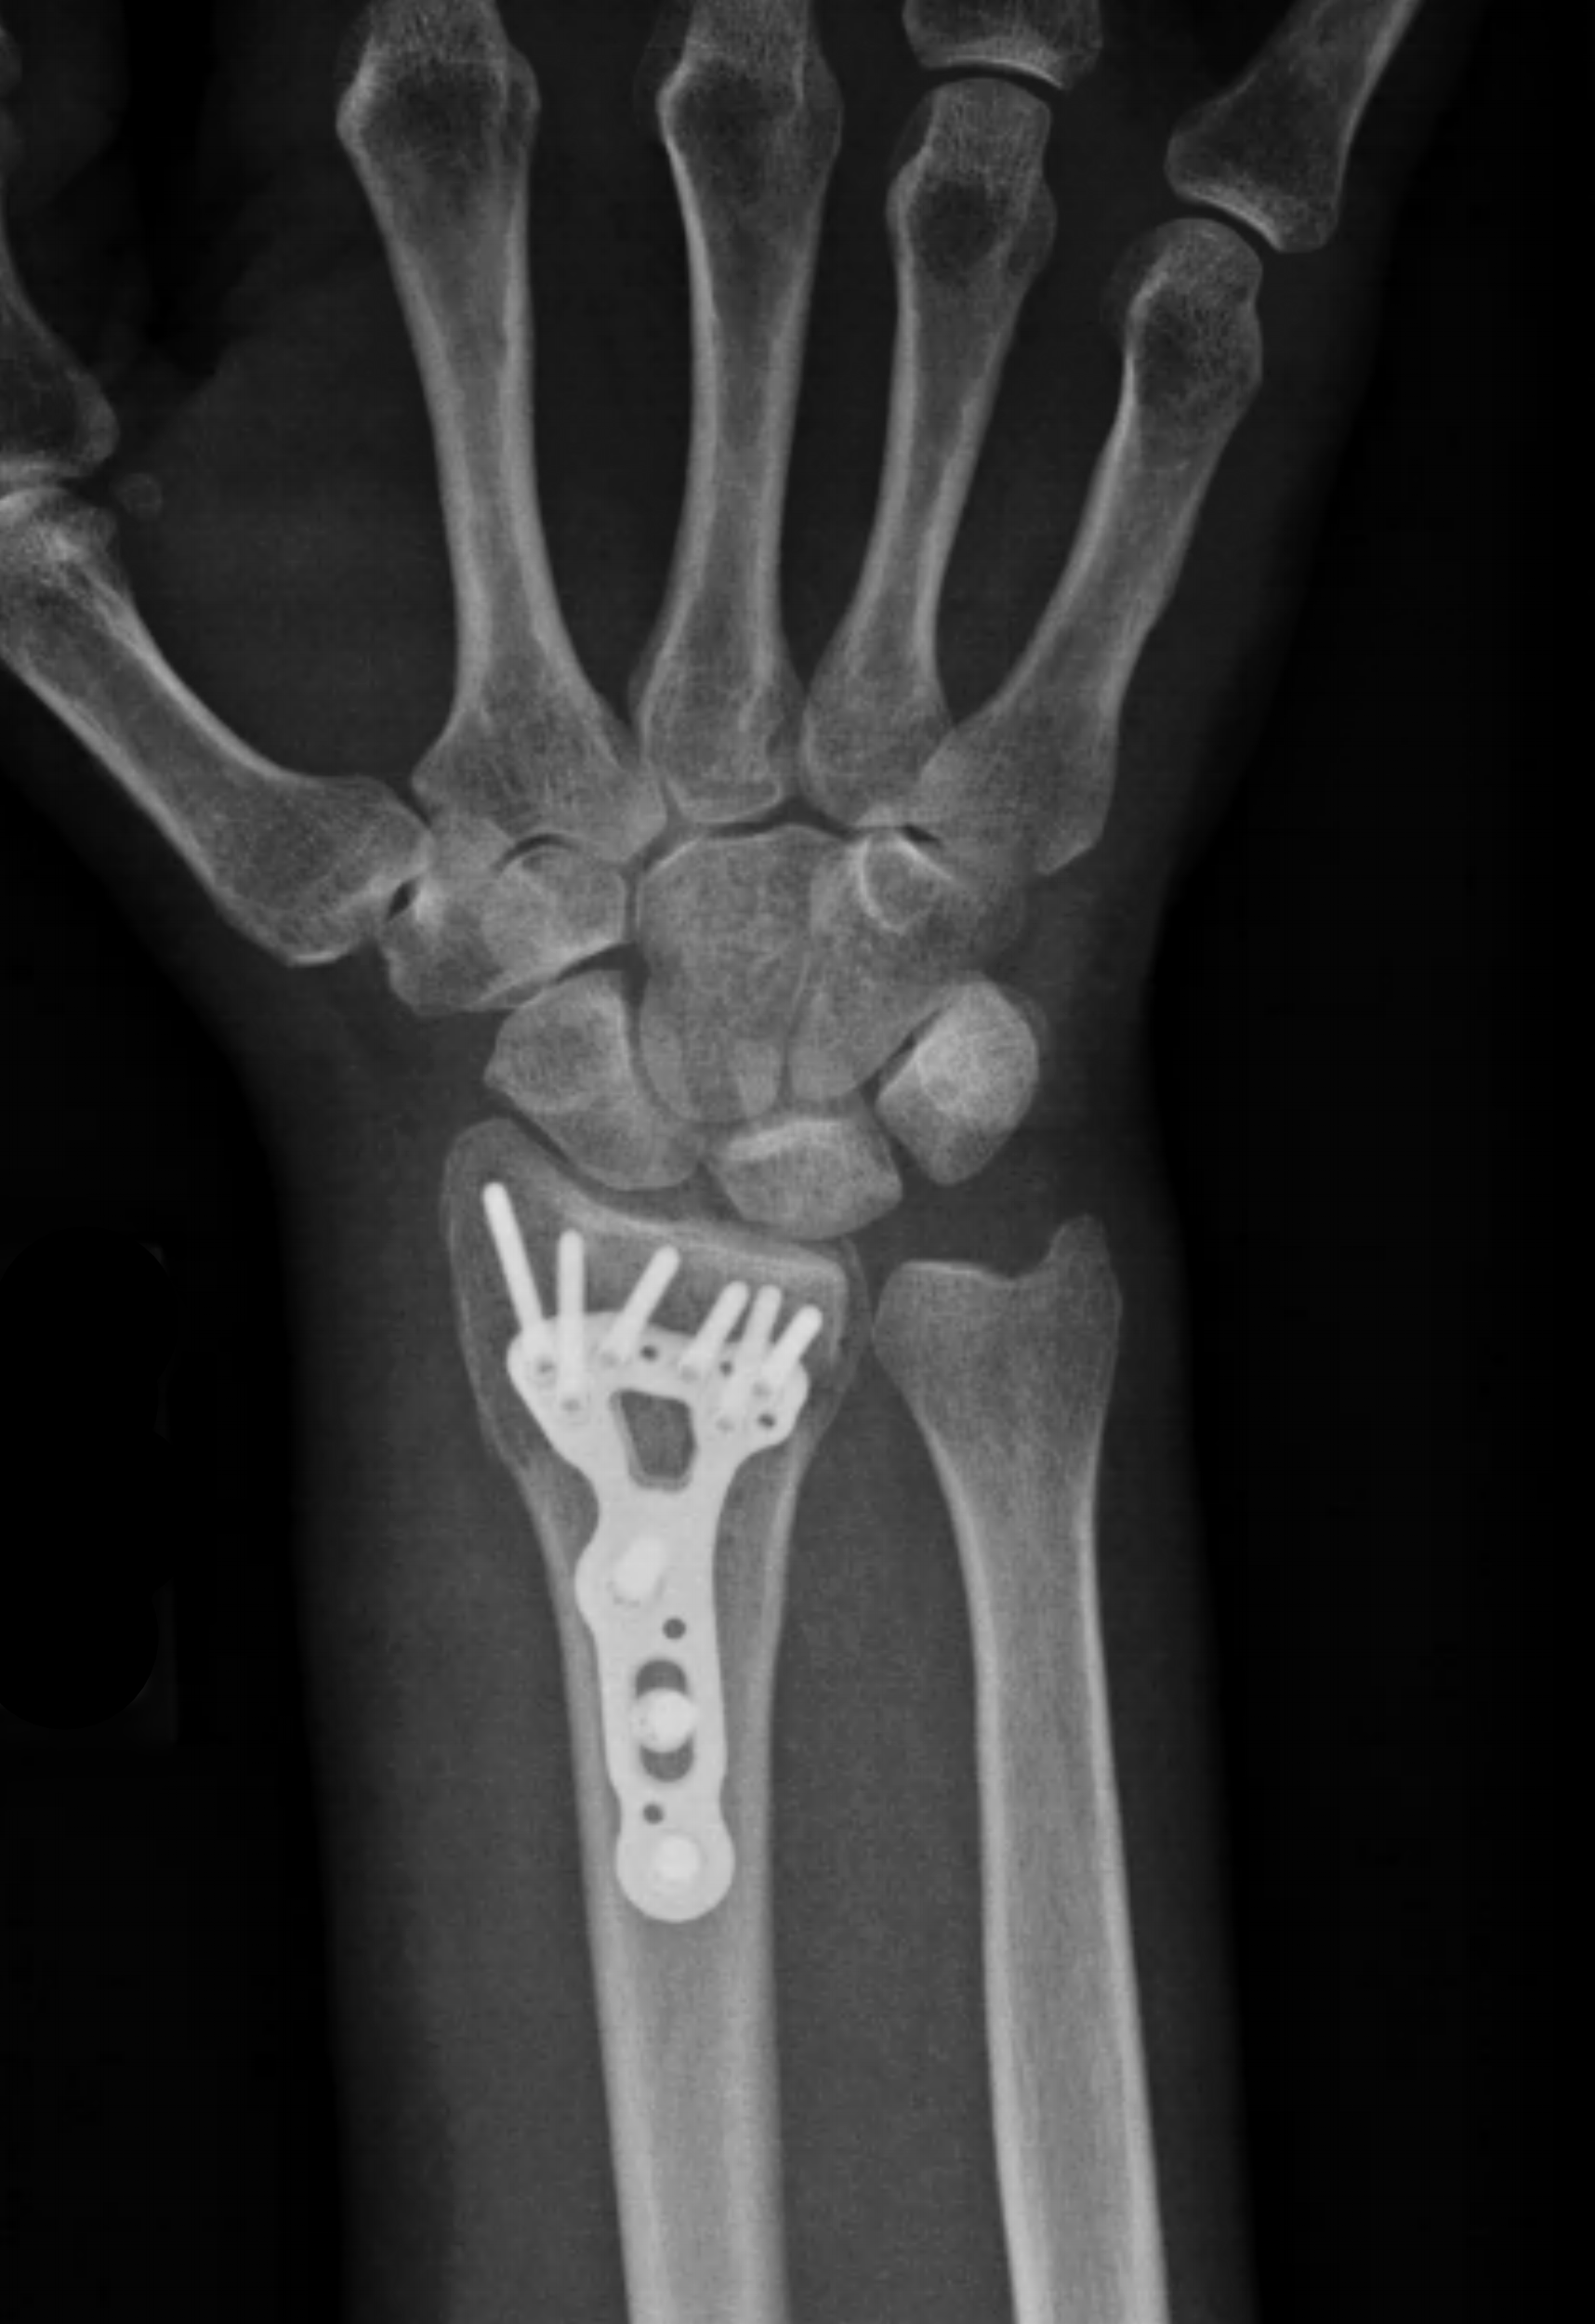

Open reduction internal fixation wrist recovery Pins And Needles After Wrist Surgery The pins can be placed without the need for an incision and are done in the operating room under a regional anesthetic. However, some cases require an operation to restore the normal structure of the bones and to provide stability and prevent. After the cast is removed, it’s normal for the wrist to be stiff for 1 to 2 months.. Pins And Needles After Wrist Surgery.